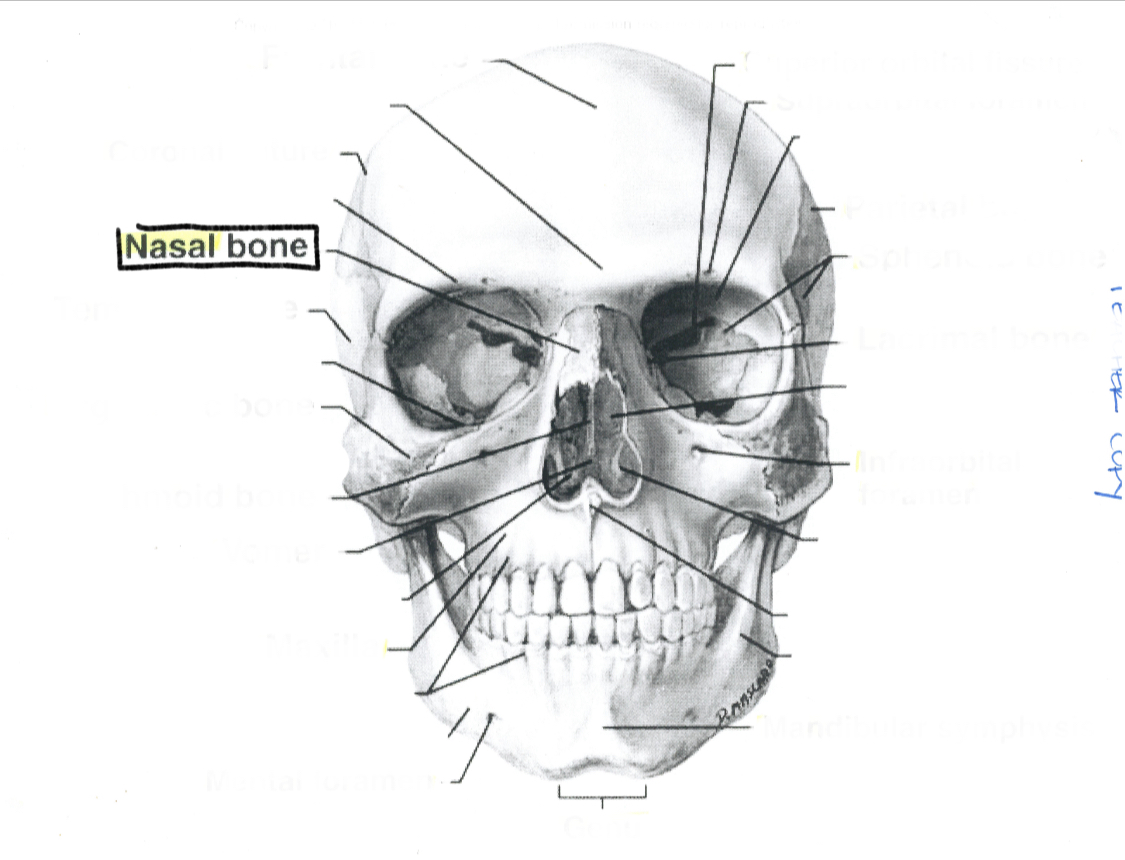

Nasal bone

What is this?